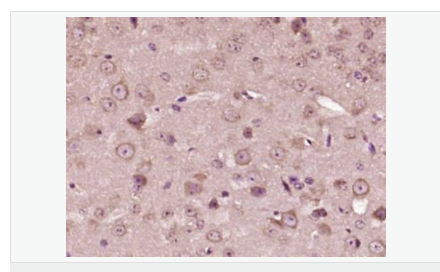

| 產(chǎn)品應(yīng)用 | ELISA=1:5000-10000 IHC-P=1:100-500 IHC-F=1:100-500 IF=1:200-800 (石蠟切片需做抗原修復(fù)) not yet tested in other applications. optimal dilutions/concentrations should be determined by the end user. |

| 產(chǎn)品介紹 | This gene encodes a member of the corticotropin-releasing factor family. The encoded preproprotein is proteolytically processed to generate the mature neuropeptide hormone. In response to stress, this hormone is secreted by the paraventricular nucleus (PVN) of the hypothalamus, binds to corticotropin releasing hormone receptors and stimulates the release of adrenocorticotropic hormone from the pituitary gland. Marked reduction in this protein has been observed in association with Alzheimer's disease. Autosomal recessive hypothalamic corticotropin deficiency has multiple and potentially fatal metabolic consequences including hypoglycemia and hepatitis. In addition to production in the hypothalamus, this protein is also synthesized in peripheral tissues, such as T lymphocytes, and is highly expressed in the placenta. In the placenta it is a marker that determines the length of gestation and the timing of parturition and delivery. A rapid increase in circulating levels of the hormone occurs at the onset of parturition, suggesting that, in addition to its metabolic functions, this protein may act as a trigger for parturition. [provided by RefSeq, Nov 2015] Function: This hormone from hypothalamus regulates the release of corticotropin from pituitary gland. Subunit: Interacts (via C-terminus) with CRFR1 (via N-terminal extracellular domain). Subcellular Location: Secreted. Similarity: Belongs to the sauvagine/corticotropin-releasing factor/urotensin I family. SWISS: P06850 Gene ID: 1392 Database links: Entrez Gene: 1392 Human Entrez Gene: 12918 Mouse Omim: 122560 Human SwissProt: P06850 Human SwissProt: Q8CIT0 Mouse Unigene: 75294 Human Unigene: 290689 Mouse Unigene: 10349 Rat Important Note: This product as supplied is intended for research use only, not for use in human, therapeutic or diagnostic applications. CRF陽性神經(jīng)元的胞體廣泛分布于下丘腦的室旁核、背縫核和藍斑核,這些區(qū)域也是去甲腎上腺素(NE)神經(jīng)元與5-羥色胺(5-HT)神經(jīng)元密集的區(qū)域。 CRF既具有神經(jīng)遞質(zhì)的性質(zhì)又具有神經(jīng)激素的性質(zhì)。CRF是聯(lián)系神經(jīng)系統(tǒng)與內(nèi)分泌系統(tǒng)的橋梁,在情感障礙疾患如焦慮和抑郁的發(fā)病中發(fā)揮重要作用. |